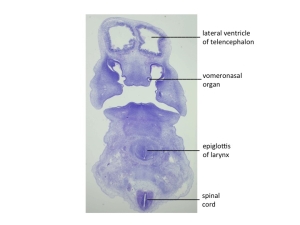

Stage 18

CfS 18

d31-35